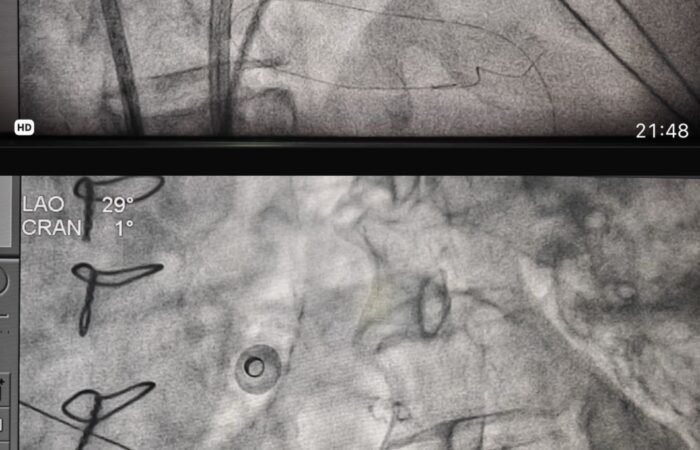

Director, Cath Lab | Head, Electrophysiology | Senior Consultant Interventional Cardiologist & Electrophysiologist

A highly accomplished and award-winning cardiologist, Dr. Arun Gopi is recognized as a pioneer in cardiac electrophysiology and complex coronary interventions in India. With multiple national “firsts” to his name, he brings unmatched expertise in managing heart rhythm disorders and interventional therapies.

Pioneering Procedures Performed First in India & Kerala